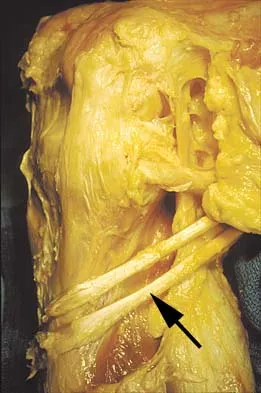

Figure 11 shows the anatomic dissection of the medial side of the knee joint after removal of the superficial fascia. The arrow is pointing to what structure?

What muscle attaches to the site shown by the arrow in Figure 2?